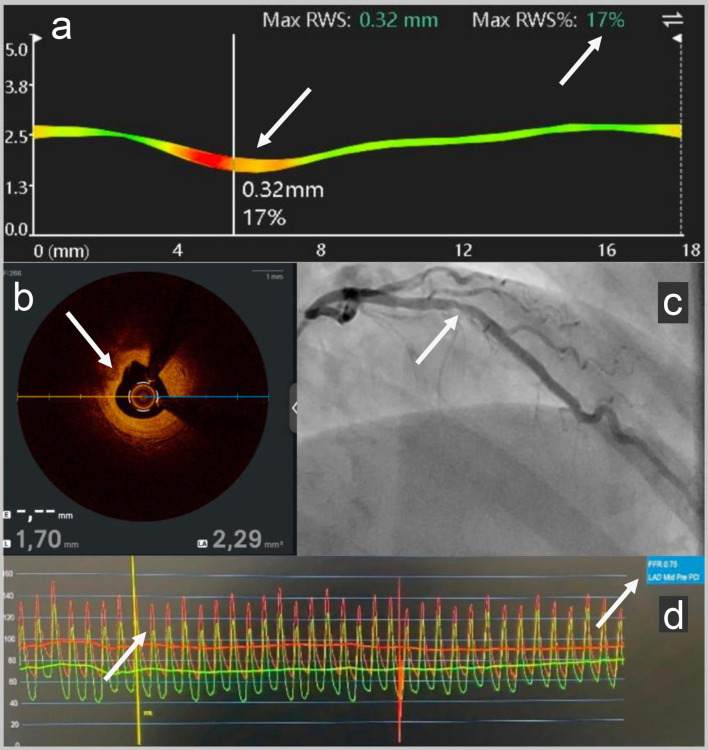

冠状动脉微血管功能障碍(CMD)是经皮冠状动脉介入治疗(PCI)后持续心绞痛的公认原因,特别是在没有心外膜冠状动脉狭窄的患者中。我们报告一个58岁的顶级运动员和世界游泳冠军,尽管成功的PCI治疗左中前降支病变,但持续呼吸困难。随访血管造影光学相干断层扫描显示无支架内再狭窄,支架贴置良好。血管造影衍生的微循环阻力(AMR, Pulse Medical)和心脏磁共振成像显示CMD是潜在的病因。本案例展示了AMR在识别pci后CMD方面的实用性和可行性,并支持其在诊断检查中的使用。

Coronary microvascular dysfunction (CMD) is a recognized cause of persistent angina post-percutaneous coronary intervention (PCI), especially in patients without epicardial coronary stenosis. We report a case of a 58-year-old top-level sportsman and world champion ice swimmer with persistent dyspnea despite successful PCI for a mid-left anterior descending artery lesion. Follow-up angiography with optical coherence tomography showed no in-stent restenosis with good stent apposition. Angiography-derived microcirculatory resistance (AMR, Pulse Medical) and cardiac magnetic resonance imaging revealed CMD as the underlying etiology. This case demonstrates the utility and feasibility of AMR in identifying CMD post-PCI and supports its use in the diagnostic workup.